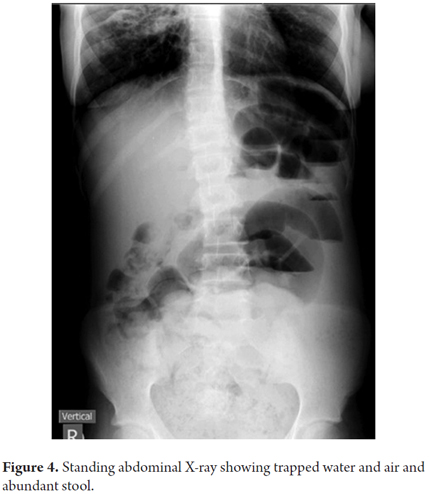

Treatment was initiated with rectal enemas of saline solution plus glycerin and oral administration of polyethylene glycol with electrolytes. Digestive enzymes (lipase/amylase/protease) were suspended. Because the patient was unable to defecate, oral feeding was suspended and replaced with feeding through a nasogastric tube. Abdominal radiography revealed the persistence of liquid and gas with abundant stool (Figure 4).